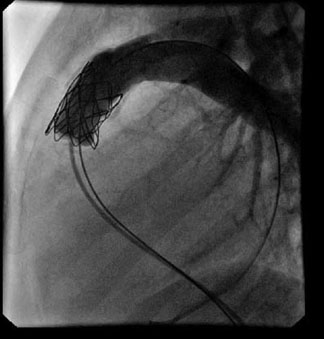

Presently, interventional catheterization is solving simple and isolated heart problems and resolving the complications that appear in the follow-up, thereby resulting in a decrease in the number of surgical procedures.

There are specific devices for closure of septal defects, both interauricular and interventricular, patent ductus arteriosus or fistulas. Openings of narrow vessels can also be performed as in aortic coarctation or valvuloplasties for valve stenosis (including foetal intervention) and, more recently, interposition of stents by catheterization for the opening of vessels and valves in pulmonary and aortic positions.

Image of a pulmonary valvuloplasty

Depending on the location of the narrowing area, they can be subvalvular (if they are localized, they are usually due to an impeller. It can that be the entire outflow tract of the left ventricle, encompassing the aortic valve ring, which complicates its treatment); valvular or supravalvular (characteristic association with the William’sSyndrome, which affects the entrance of the coronary arteries). Their treatment will be determined by the degree of narrowness and its location. In valvular forms the first thing is to perform an aortic valvuloplasty (using balloon dilation by catheterization, as seen in the next diagram) and wait for the child to grow, eventually placing a mechanical prosthesis when feasible (ideally after growth is complete, from around 12 years old).

Image of an aortic valvuloplasty